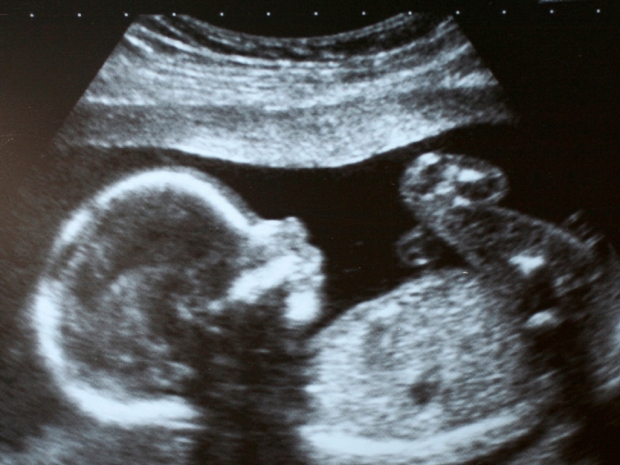

Врачи подчеркивают важность ультразвукового исследования на разных этапах беременности. УЗИ позволяет не только подтвердить факт беременности, но и отслеживать развитие плода, выявлять возможные аномалии и оценивать состояние матери. Специалисты отмечают, что каждое исследование имеет свои особенности в зависимости от срока. На ранних сроках УЗИ помогает увидеть сердцебиение и определить количество эмбрионов. Позже, на более поздних сроках, врачи могут оценить анатомию плода, его размеры и положение в матке. Фотографии, полученные во время УЗИ, становятся важной частью медицинской документации и часто вызывают эмоциональный отклик у родителей. Врачи рекомендуют проходить УЗИ в установленные сроки, чтобы обеспечить здоровье как матери, так и ребенка.

Плод достиг размера, сопоставимого с кулаком взрослого человека. На ультразвуковом исследовании, проведенном на 14-й неделе беременности, можно заметить, что все внутренние органы плода заняли свои окончательные позиции в брюшной полости, и больше не наблюдается выпячивания, как это происходило несколько недель назад. УЗИ уже позволяет различить даже узоры на ладошках малыша. Лицо начинает приобретать более четкие контуры, а длина шеи увеличивается. Плод активно сосет свои пальцы, что свидетельствует о развитии естественного рефлекса.